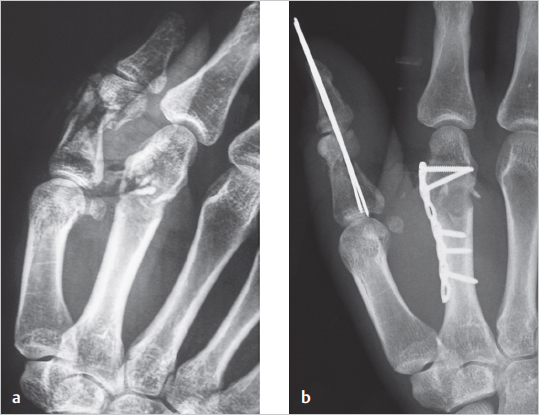

8 Principles of Osteosynthesis Abstract Bone tissue is derived from various embryological lineages which follow a process of either intramembranous or endochondral ossification. Bone is formed of organic and inorganic fractions composed of cells, proteins, and minerals that provide its physiological and structural characteristics. The organization of intrinsic collagen fibers determines whether bone tissue matures to become woven or lamellar. Bone consolidation can be direct or indirect. The latter occurs through five overlapping phases of callus formation. Fracture treatment should include reduction, absolute or relative stabilization, fixation of the fragments, and rehabilitation. However, fracture treatment is not exempt from complications, such as infection, delayed union, nonunion, and malunion. Distraction osteogenesis is a procedure that uses the process of generating new bone tissue between osteotomized bone fragments and can be used when other forms of bone fracture treatment or congenital malformations fail to provide enough bone length. This chapter presents the current knowledge of bone microanatomy and fracture pathophysiology, which constitute the foundations for bone healing and synthesis, and gives a comprehensive review of the most commonly used surgical techniques for fracture fixation and its complications. Keywords: bone microanatomy, distraction osteogenesis, fracture stabilization, ossification, osteomyelitis, osteosynthesis devices, pseudarthrosis Osteogenesis is the process of bone formation. The skeletal components are derived from three embryological lineages. Neural crest cells give rise to the pharyngeal arches and the axial skeleton; paraxial mesoderm forms the craniofacial skeleton and most of the axial skeleton through the division of the somites; and finally, the limbs’ skeleton develops from the lateral plate mesoderm. Differentiation of mesenchymal tissue into bone can follow an intramembranous or an endochondral mechanism. Intramembranous ossification is characterized by direct bone formation in a connective tissue membrane in the absence of cartilage. It occurs in flat bones, in the fracture callus, and in distraction osteogenesis. Endochondral ossification occurs through a cartilage intermediate, called the primary ossification core in the embryonic period, and a secondary ossification core after birth. This type of ossification occurs in long bones and in the fracture callus as well. Bone tissue consists of two essential components, namely extracellular matrix (ECM) and cells. The ECM contains an organic phase and a mineral fraction. The cells constitute a small percentage included in the organic fraction of bone tissue. The organic fraction of the ECM constitutes 30% of dry bone mass and is mainly formed by three protein groups: collagenous, noncollagenous, and glycoproteins. Collagenous proteins form the osteoid, which is the chief element of bone matrix, and provide elasticity and flexibility. Collagen type I is organized in a fibrillar form and has a mineralization potential, providing bone elasticity and tensile strength. Hydroxyproline is a major component of collagenous proteins, and its increased urinary levels reflect bone resorption. Noncollagenous proteins include osteocalcin, a linear peptide hormone produced by osteoblasts during bone formation and incorporated into the bone matrix, and bone morphogenetic proteins (BMPs), which are involved in the formation of new bone, cartilage, and connective tissue. Finally, proteoglycans and glycoproteins form the fundamental amorphous substance that surrounds cells and collagen. They are composed mainly of hyaluronic acid chains bounded to subunits of chondroitin sulfate and keratin sulfate. The inorganic or mineral phase accounts for 50–70% of bone composition and is responsible for providing mechanical rigidity and strength to the ECM. It is formed by hydroxyapatite crystals consisting of 80% tricalcium phosphate and 10% calcium carbonate. Different growth factors, such as the Wnt family and BMPs, stimulate mesenchymal stem cell differentiation into osteoblastic progenitors, such as pro-osteoblasts, which then become osteoblasts and ultimately osteocytes. These cells are all located in the endosteal and periosteal layers. Osteoblasts are found on the surface of bone, and their main function is osteoid production. They also synthesize alkaline phosphatase and osteocalcin and have receptors for parathyroid hormone (PTH), 1,25(OH)2-vitamin-D, glucocorticoids, prostaglandins, and estrogens. Osteocytes are found within the bone matrix and constitute 90–95% of the cellular component. They develop from the osteoblasts located in the lacunae and are characterized by large cytoplasmic processes that extend radially through the osteons and to the canaliculi, allowing communication with other osteocytes and osteoblasts. Osteocytes are key in regulating homeostasis of extracellular calcium and phosphorus. Osteoclasts are located in the trabecular bone surface in spaces called Howship’s lacunae and at the head of the cortical perforating cones. They are activated by osteoblasts to exert their main function, which is to lyse bone. The contact zone of their cell membrane has a hairy pattern that increases the area of resorption. Once in contact with the bone surface, the osteoclast’s cell membrane delimits an area fixed and sealed by integrins, where pH is reduced through a proton pump, and acid proteases are released, dissolving the mineral matrix and degrading the collagen component. Depending on the organization of collagen fibers, two types of bone can be identified: woven and lamellar. Woven bone owes its name to its characteristically irregular organization of cells and collagen fibers, which, together with its increased water content, make it highly deformable and flexible. Woven bone is the primary or immature bone found in the skeletons of embryos and newborns, and it is gradually replaced by mature (e.g., lamellar) bone during skeletal growth. In adults woven bone may persist as part of the ear bones, tendon and ligament insertions, and cranial bone sutures. In addition, woven bone is the first to appear in the callus of healing fractures. Lamellar bone, also called secondary or mature bone, completely replaces woven bone by 4 years of age and is organized in a specific and regular pattern according to the supported loads. Cortical bone is a type of lamellar bone forming 80% of an adult’s skeleton. It is formed by a set of elementary functional units called osteons, composed of a series of concentrically arranged bone plates. At the center of each osteon, blood and lymphatic vessels and nerves run through the haversian canals, which interconnect with each other and with the periosteum through Volkmann’s canals. The spaces between the osteons are occupied by interstitial lamellar systems ( The periosteum is a well-vascularized layer that covers the outermost part of cortical bone and is divided into an outer sheet, composed of poorly active fibrous tissue; and an active inner layer or cambium layer, lying in direct contact with the cortical bone surface and rich in osteoblast cells, which orchestrate callus formation and repair of bone following fracture. Cancellous bone forms 20% of the skeleton and consists of a set of bony trabeculae arranged in a randomly oriented three-dimensional network that provides load support. The spaces between the trabeculae are occupied by bone marrow and fatty tissue. Cancellous bone has lower rigidity than cortical bone, but a metabolic activity that is eight times higher ( Note The cambium layer is rich in osteoblasts. It activates after a fracture and forms the fracture callus. A fractured bone can heal or consolidate directly or indirectly depending on fracture treatment and stability. Direct, primary, or cortical consolidation takes place in anatomically reduced fractures with absolute stability. It is produced by the passage of vessels through the bone contact areas and osteoblastic apposition of new bone in areas of no contact. Direct consolidation occurs without callus formation. Indirect or secondary consolidation occurs in fractures treated with flexible fracture stabilization, which allows interfragmentary mobility. Indirect consolidation occurs through callus formation along a set of five overlapping phases, namely hematoma, inflammation and angiogenesis, reparative, ossification, and remodeling. In the first phase of hematoma, the blood clot releases interleukins-1 and -6 (IL-1 and IL-6) and tumor necrosis factor-α (TNF-α) that trigger the inflammation cascade. The inflammatory and angiogenesis phase then ensues with neutrophils, macrophages, and lymphocytes being recruited to the site of injury to remove debris and initiate repair. During this phase the initial hematoma is gradually replaced by a fibrin clot, and osteoclasts begin resorption of the bony ends. Vasodilation and hyperemia of the surrounding soft tissues promote the formation of new capillaries that grow through the site of injury, and precursor cells begin to proliferate and differentiate into osteoblasts. Later in this phase, fibrin, collagen, and reticular fibers are replaced by granulation tissue. The reparative phase starts at the offset of inflammation and is characterized by the formation of a soft callus composed mainly of cartilage and varying amounts of connective tissue and blood vessels, in response to mechanical and biological factors. The ossification phase starts at the third week to form the hard callus and lasts between 12 and 16 weeks, until the bony ends are firmly joined together. During this phase, the soft callus undergoes endochondral and intramembranous ossification. Finally, in the remodeling phase the immature woven bone with its irregular microstrucure is gradually replaced by mature, laminar, anisotropic bone in response to the mechanical load ( Fig. 8.1 Bone microanatomy. (Reproduced from Schuenke, Schulte, and Schumacher, Atlas of Anatomy, 2nd edition, ©2014, Thieme Publishers, New York. Illustration by Karl Wesker/Markus Voll.) Fig. 8.2 Stages of bone callus formation during secondary fracture healing. (a) Hematoma filling the fracture gap. (b) Granulation tissue and connective tissue replacing the hematoma in the fracture gap with ingrowth of blood vessels. (c) Fibrocartilage replacing the connective tissue in the fracture gap. (d) Woven bone replaced by lamellar bone through haversian remodeling. (Reproduced from Ehrenfeld, Manson, Prein, Principles of Internal Fixation of the Craniomaxillofacial Skeleton Trauma and Orthognathic Surgery, ©2012, Thieme Publishers, New York.) Note Bone callus is formed through five established phases: hematoma, inflammatory and angiogenesis, reparative, ossification, and remodeling. The objective of fracture treatment is to promote consolidation and restore the bone’s mechanical properties for maximum functional recovery. Different factors affect the process of bone regeneration, such as age, genetics, and mechanical factors. Anatomical relationships between bone fragments can be restored by open or closed manipulation. The aim of anatomical reduction is to correct shortening, angulation, and rotation. Fracture stabilization can be achieved by conservative (e.g., plasters) or surgical treatment. The objective is to reduce the mobility of the bony ends to allow bone healing. External fixators are not aimed at providing definitive stabilization, but rather a reasonable reduction until other issues are solved (e.g., vascular injury or soft tissue reconstruction). The biological response and the type of consolidation occurring at the fracture site are highly dependent on the degree of relative or absolute stabilization yielded by the selected treatment. For example, fractures stabilized with a plaster or elastic fixation (e.g., Kirschner wires), undergo secondary consolidation. Relative stability allows microscopic movements between the fragments following load application. Techniques of relative stability include intramedullary nailing, which controls fracture angulation and displacement, but not rotation. The addition of locking screws (e.g., locked intramedullary nailing) can help to correct shortening and rotation. Bridging plates fixed with locked screws provide relative stability by bridging the area of greater comminution while maintaining length and alignment. Finally, external fixators can correct bone alignment, but the stiffness of the frame is limited because the rods are fixed to pins several millimeters or even centimeters above the fracture ( Fig. 8.3 (a) Comminuted fracture of the proximal phalanx of the thumb and second metacarpal. (b) Thumb fixation with Kirschner wires and second metacarpal fixation with 2-mm bridging plate. Absolute stability is achieved with rigid fixation by interfragmentary compression at the fracture site resulting in primary or direct consolidation. Techniques of absolute stability include compression screws or plates that transform rotational forces into linear fracture compression, and tension bands that convert distraction tensile forces into compression forces at the fracture site. Note Absolute stability results in primary consolidation, whereas relative stability leads to fracture healing through callus formation (e.g., secondary consolidation). Kirschner wires are available in different diameters, from 0.8 to 3 mm. They are versatile and can be used in any small bone fracture, but comminuted fractures are their primary indication. Wires can be inserted through a closed or open approach, causing minimal trauma to the surrounding tissues, and they may be used as temporary or definitive fixation providing relative stability to the fracture. One of their limitations is that they do not allow interfragmentary compression. Screws are helical devices that convert rotational forces into linear motion ( Screws can also be self-tapping or self-drilling. Self-tapping screws have a taplike flute in their leading threads, which allows them to tap their own hole as they are driven into, but need bone drilling prior to insertion. Self-tapping screws are not recommended for use as lag screws. Self-drilling screws have a preliminary drill-like fluted tip that allows insertion without predrilling of bone ( Lag or compression screws provide reduction between two fragments and achieve absolute stability. The principle of lag screws is based on making the screw glide without purchase through the proximal fragment and thread through the distal fragment so that, with each turn, the distal fragment is brought against the proximal fragment. This can be obtained either with partially threaded screws or by overdrilling the near cortex (

Fig. 8.3).